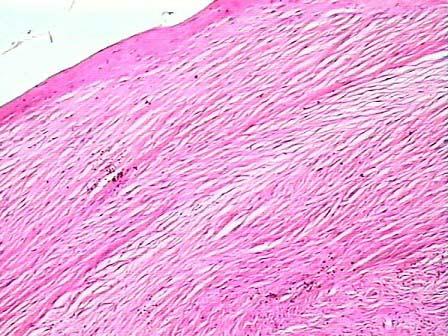

问题 男性病患,手术切除左手臂上一皮下肿块,结节状,有包膜,切面灰白色,质均,镜下改变如图1、2、3所示,可能的诊断是 ( )

选项 A.纤维肉瘤 B.纤维瘤 C.平滑肌瘤 D.脂肪瘤 E.平滑肌肉瘤

答案 B